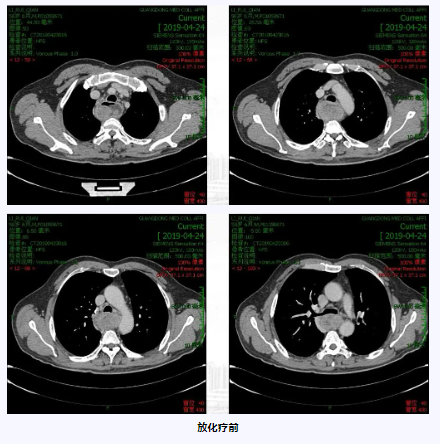

病例一:

术后辅助化疗后行大分割放疗治疗乳腺癌保乳术后患者,降低局部复发率,具有可控的安全性和长期生存期。